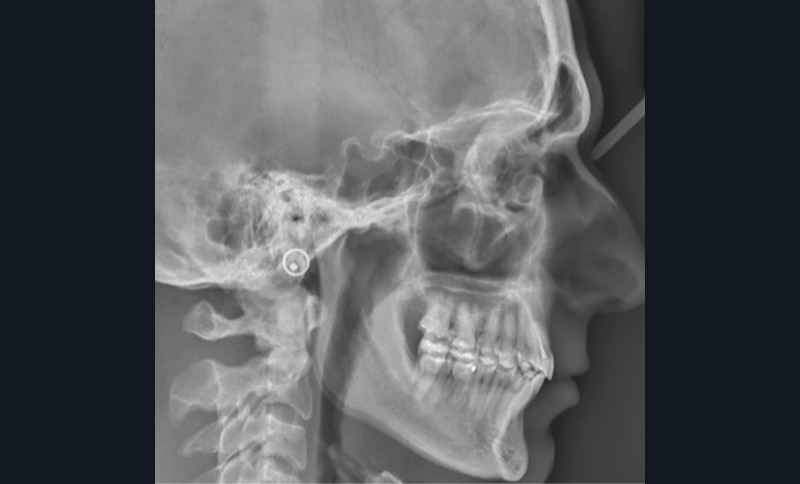

Examens complémentaires (fig. 3)

La téléradiographie de profil et l’analyse céphalométrique montrent une classe I squelettique tendance classe II dans un contexte d’hypodivergence, caractéristique des classes II division 2 [3,4]. L’axe de l’incisive mandibulaire est correct, au sein d’une symphyse épaisse, tandis que l’incisive maxillaire présente une rétroalvéolie importante. La supraclusion antérieure est d’origine mixte, majoritairement mandibulaire, en lien avec une courbe de Spee marquée.